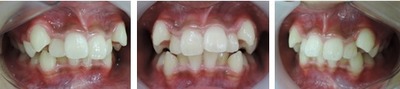

歯並びの悪い症例

口腔機能を順調に発育発達させる為には早期治療が効力を発揮します。

多数の治療法がありますが、当院ではブラケットという矯正装置を歯に装着する事で、上下顎骨の大きさと、咬み合わせの高さを改善していきます。

前歯がクロスしていて将来、口腔機能に悪影響を及ぼす事となります。

①前歯のクロスを改善するためには咬み合わせを高くする必要があります。

当矯正歯科医院では上顎の乳臼歯にレジンを盛る事で、クロスした前歯の被蓋(前歯の咬み合わせ)を改善していきます。

前歯のクロスが改善されて治療しやすくなっています。

その後、ブラケット装着を使用して上顎骨の拡大を始めます。

上顎骨の拡大を始めてから、下顎骨の拡大を始めます。

この上下顎骨の拡大と咬み合わせの高さの改善を1年6ヶ月間、治療を続けます。

すると、治療前と治療後は以下の様に変わります。

治療前の症例

1年6ヶ月後の症例